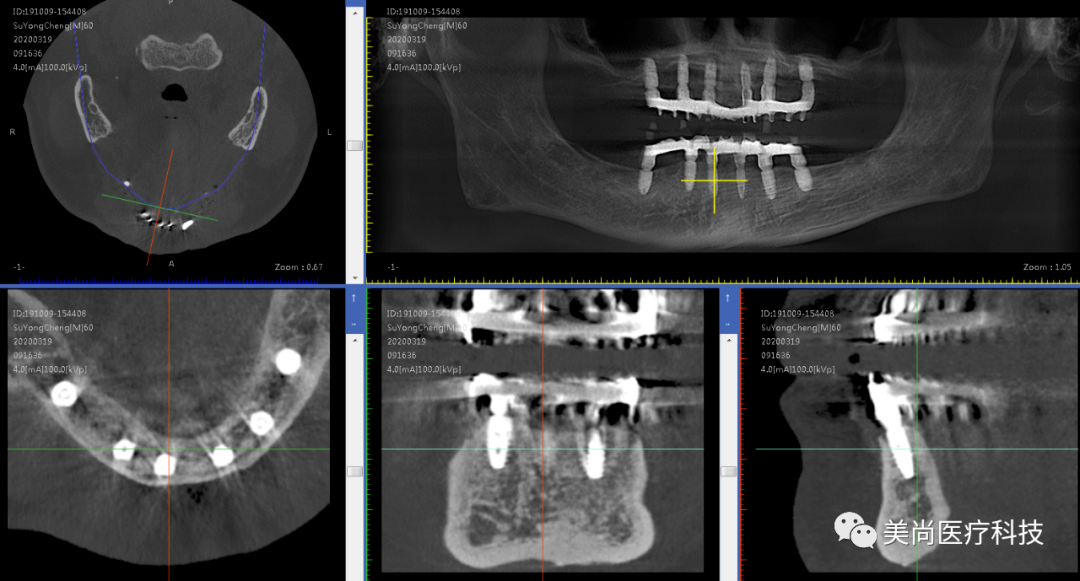

术前X-ray

制作种植导板